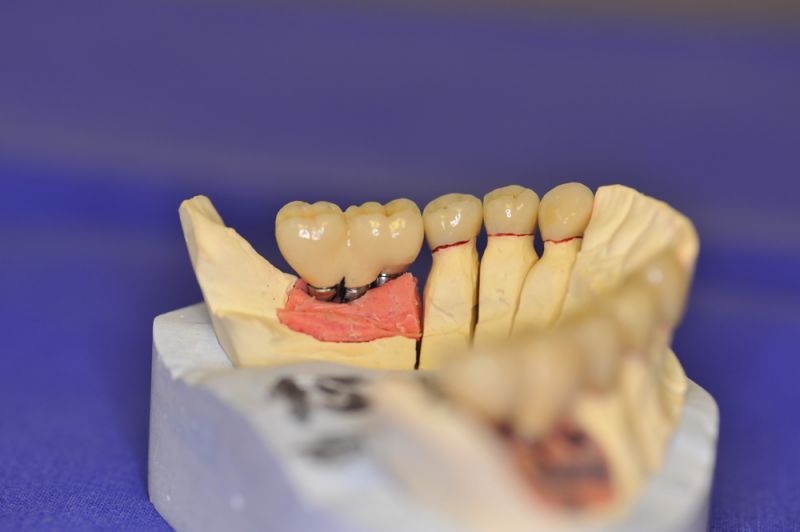

1. Notwendigkeit einer implantatgestützten Kronenversorgung mit der Vorgeschichte, dass die Patientin eine Vielzahl von Behandlern aufgesucht hatte, die eine Implantation im Unterkiefer als nicht durchführbar einschätzten.

3. Sehr dünne Implantate, die von ursprünglich zwei je Kieferhälfte auf letztendlich drei je Kieferhälfte umgeplant werden mussten.

4. Notwendigkeit die Mundhygienefähigkeit der Arbeit auch unter sehr beengten Verhältnissen zu schaffen, um der Arbeit eine günstige Prognose mitzugeben.